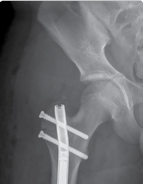

| 43. Monolateral rail (Figure 15.7) 1. If no risk of joint subluxation | |||

| 2. Three half-pins proximal and, at least, three distal to corticotomy | |||

| 44. Circular frame | |||

| 1. If risk of joint subluxation | |||

| 2. Span knee/pelvis | |||

| 3. Arches/two-thirds rings to allow mobility | |||

| 4. Same principles as earlier | |||

| Figure 15.7 Radiograph of femoral limb reconstruction system (LRS) rail. | |||